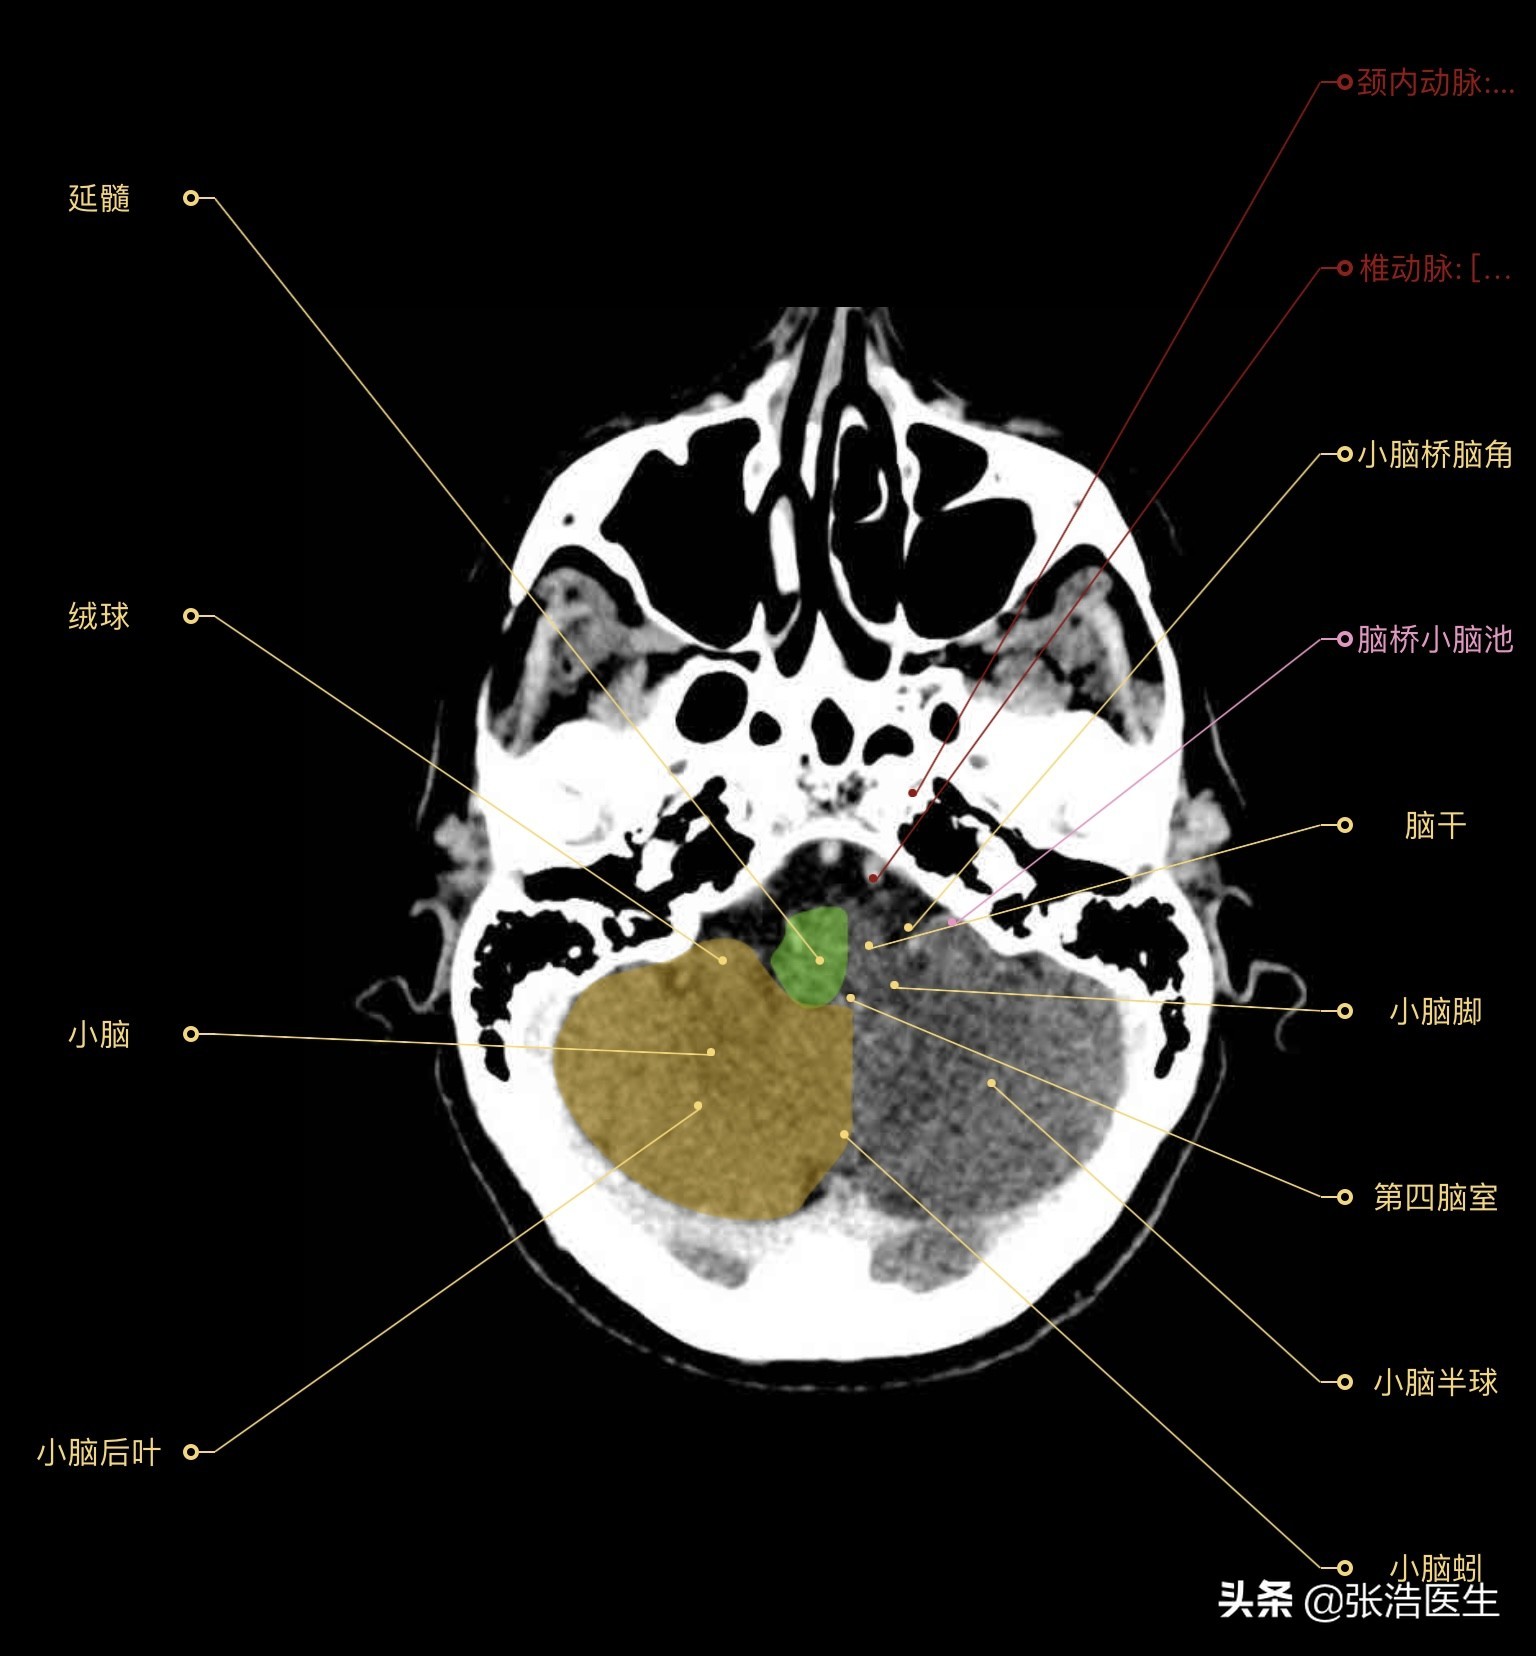

颅脑CT横断面高清解剖图层9(小脑层面)

精选9层常用解剖断面

每一层都带有详细标注,值得收藏学习